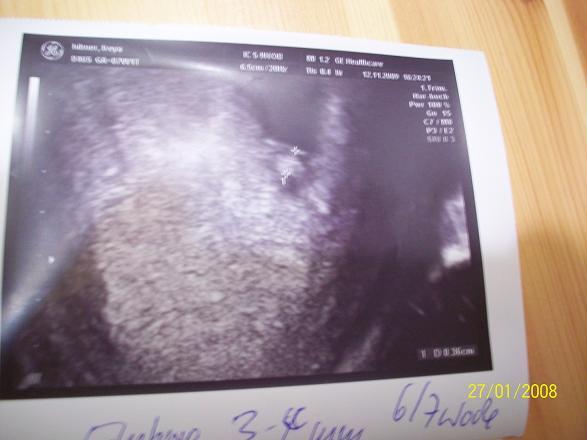

Und ich bin sooo happy. Es ist zum Glück nur EIN Baby und das war gut zu sehen. Das Herzchen schlug auch ganz doll. Allerdings bin ich heute nicht 6+1 sondern 6+3 anhand der Grösse des Babys. Neuer ET ist also erstmal der 05.Juli. Mit der SG Impfung warte ich jetzt bis der Impfstoff für Schwangere da ist. Dann wird mein FA weitere Informationen haben und mir sagen ob ich es machen soll. Er fand es aber wichtig das mein Umfeld geimpft wird. Hier nochmal ein Bild vom meinem Würmchen.

Schön, dass alles so ist, wie Du es Dir gewünscht hast. Schönes US-Bild!